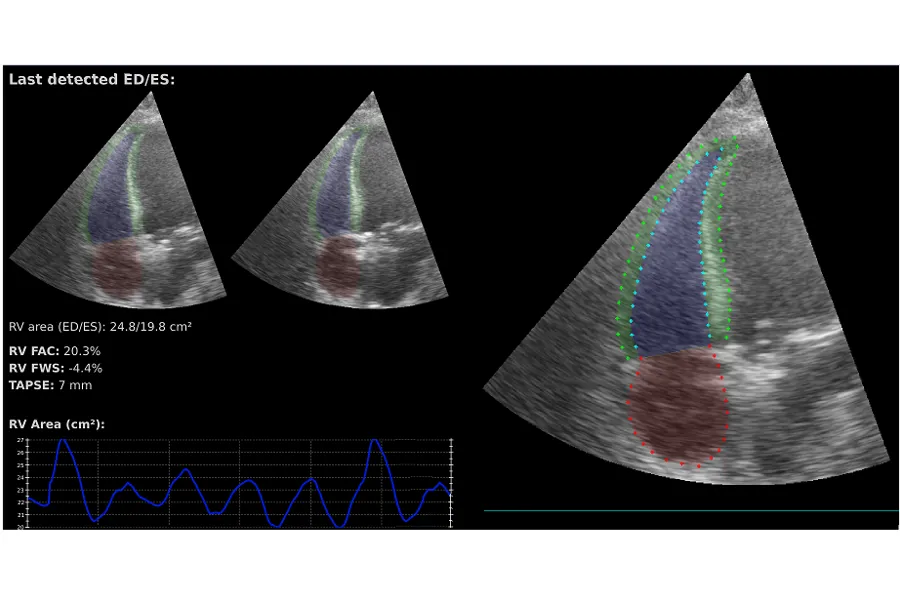

Automated analysis of the right ventricle with efficient deep learning methods in 2D echocardiography

Right ventricular function is linked to exercise capacity and plays a key role in pulmonary diseases like COVID-19. It also serves as an important marker in the progression of heart diseases affecting other chambers. Current analysis tools are lagging in functionality for evaluating the right ventricle, often due to poor image quality. We propose AI algorithms as a solution, as they can detect patterns even in noisy recordings.

Our aim is to develop accurate, fast, and computationally efficient AI tools that can be integrated into a broad range of clinical settings and ultrasound devices.

- Automated Segmentation and Quantification of the Right Ventricle in 2-D Echocardiography (Link to publication)